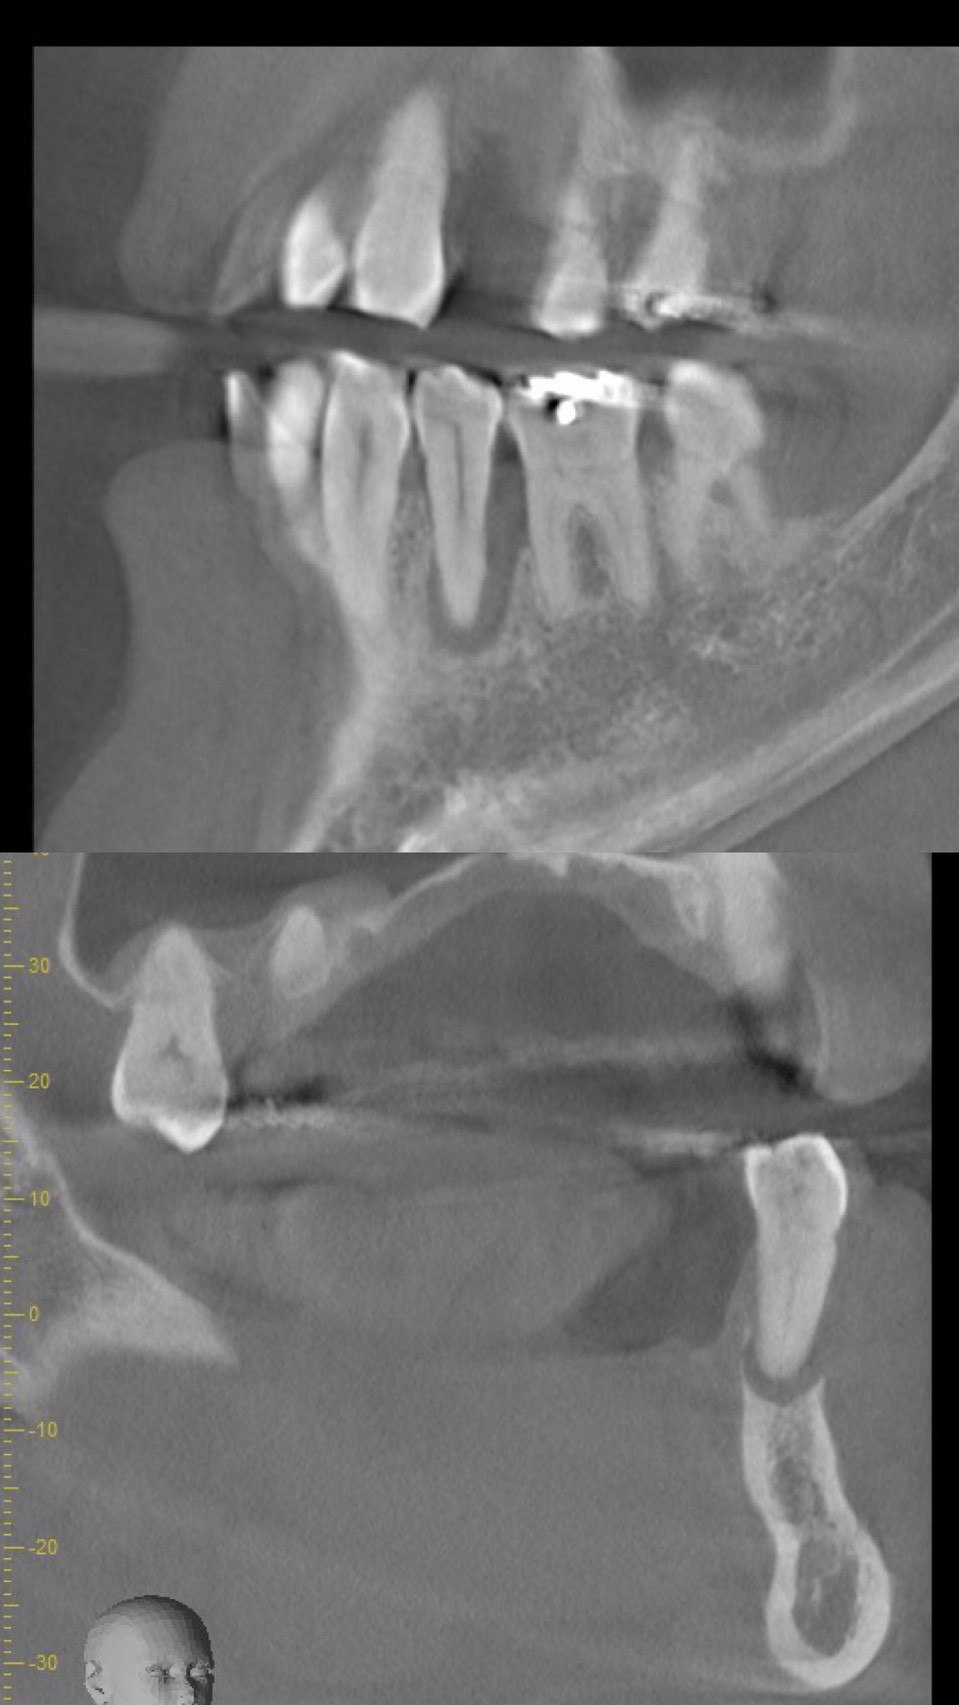

この部分をCTでみてみると、骨の壁がほとんどなくこのままにしておくと、他の歯と同じように自然に抜けてしまう未来が見えます。

先生によっては、抜歯宣告を受けてもおかしくないくらい状態は悪いです。

レントゲンでみると右下5番目(実際は左下5)の歯根の先端が黒く抜けています。この状態は、重度歯周病と根尖性歯周炎(根が膿んでる)が混在しており非常に予後が悪いとされています。